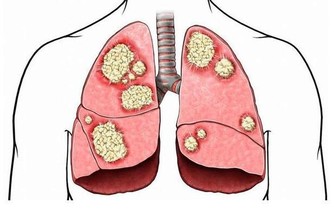

不明原因並且日漸加劇的咳嗽,也可能是血栓的跡象,表明血栓雖然較小,但已經在肺部形成。更嚴重的跡象包括咳血或產生含有血液的粘液。